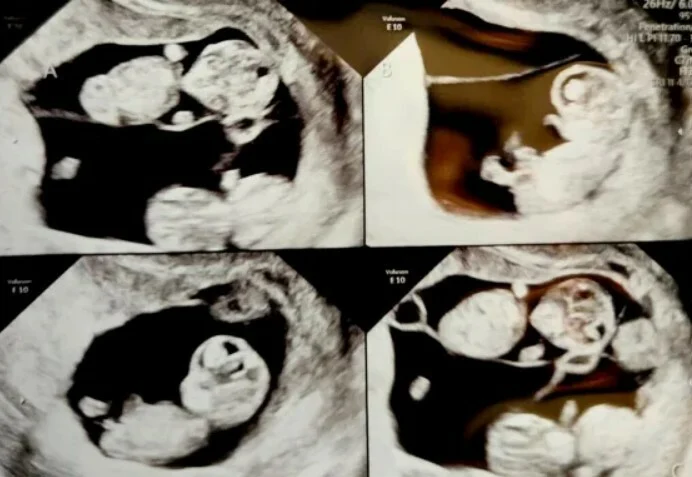

Η Mercedes δεν πίστευε στα μάτια της όταν τέσσερις σάκοι εμφανίστηκαν στην οθόνη υπερήχων. Ήταν μόλις επτά εβδομάδες έγκυος, όταν είδε «τέσσερις μικρές σταγόνες» που εμφανίστηκαν στην οθόνη του υπερήχου, όπως λέει εκείνη. «Εφόσον ήταν η τρίτη μου εγκυμοσύνη, είπα στον Jonathan ότι δεν χρειαζόταν να έρθει στο ραντεβού. Λοιπόν, είμαι εκεί χωρίς αυτόν, γελάω και μετά κλαίω. Είμαι λίγο σε υστερία. Και ο γιατρός μου λέει, ‘ας φωνάξουμε τον άντρα σου’!»».

Η Hannah Grace, η Lucy Marie, η Rebecca Claire και η Petra Anne γεννήθηκαν με καισαρική τομή στις 29 εβδομάδες κύησης. Η μικρότερη ήταν η Petra, που ζύγιζε 1 κιλό και 200 γραμμάρια, ενώ η μεγαλύτερη, η Hannah γεννήθηκε με 1 κιλό και 400 γραμμάρια. Η Mercedes, 34 ετών, και ο Jonathan, 37 ετών, που είναι και οι δύο μηχανικοί, είναι επίσης γονείς του Luke, 3 ετών, και του Aaron, 18 μηνών.